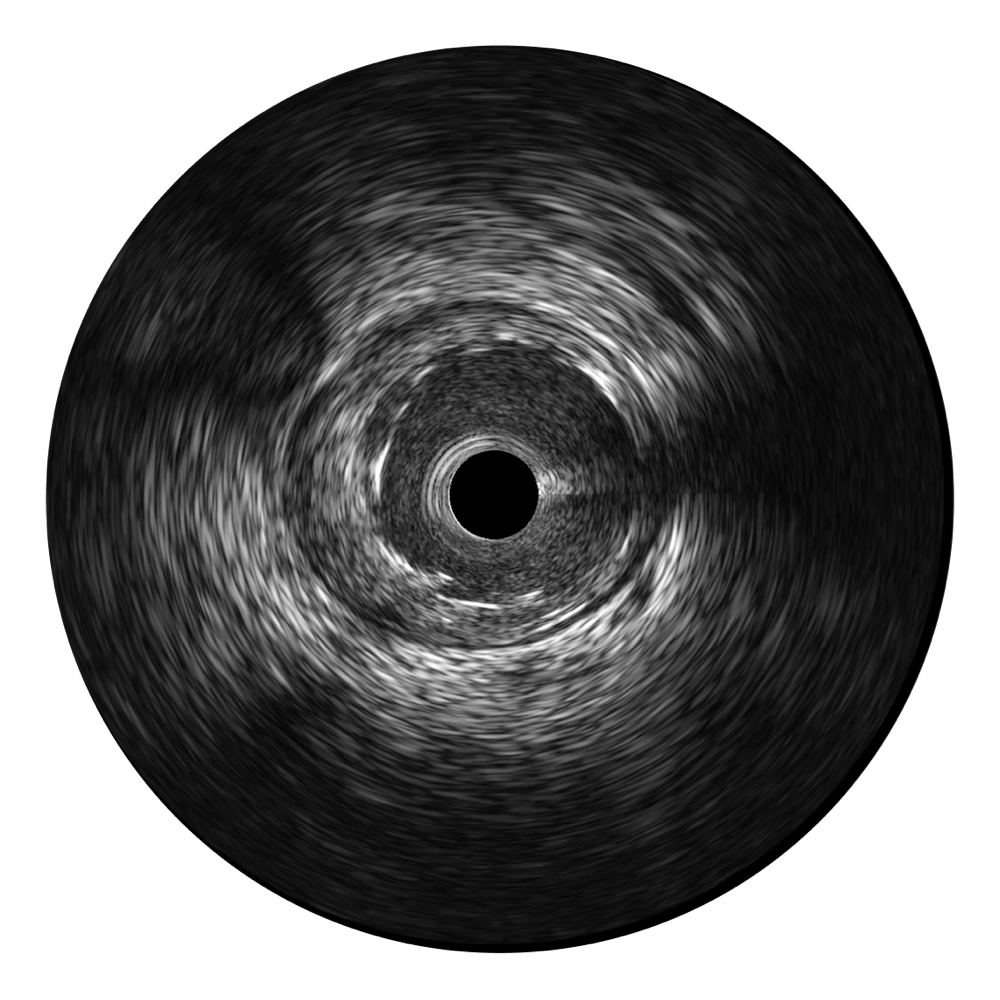

银河集团官网宽频IVUS图像

对比传统IVUS导管成像,银河集团官网宽频IVUS图像的近场支架梁显影更细腻,远场中膜外血管仍清晰可辨,兼顾远中近,兼顾分辨力与穿透深度